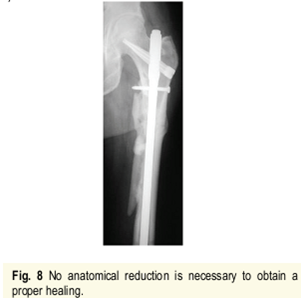

4.正确的进针点和足够的髓内钉长度,即使不能达到解剖复位,也能收到满意的愈合结果;

6.长阶段劈裂骨折非解剖复位反而增加骨痂量收到满意效果。